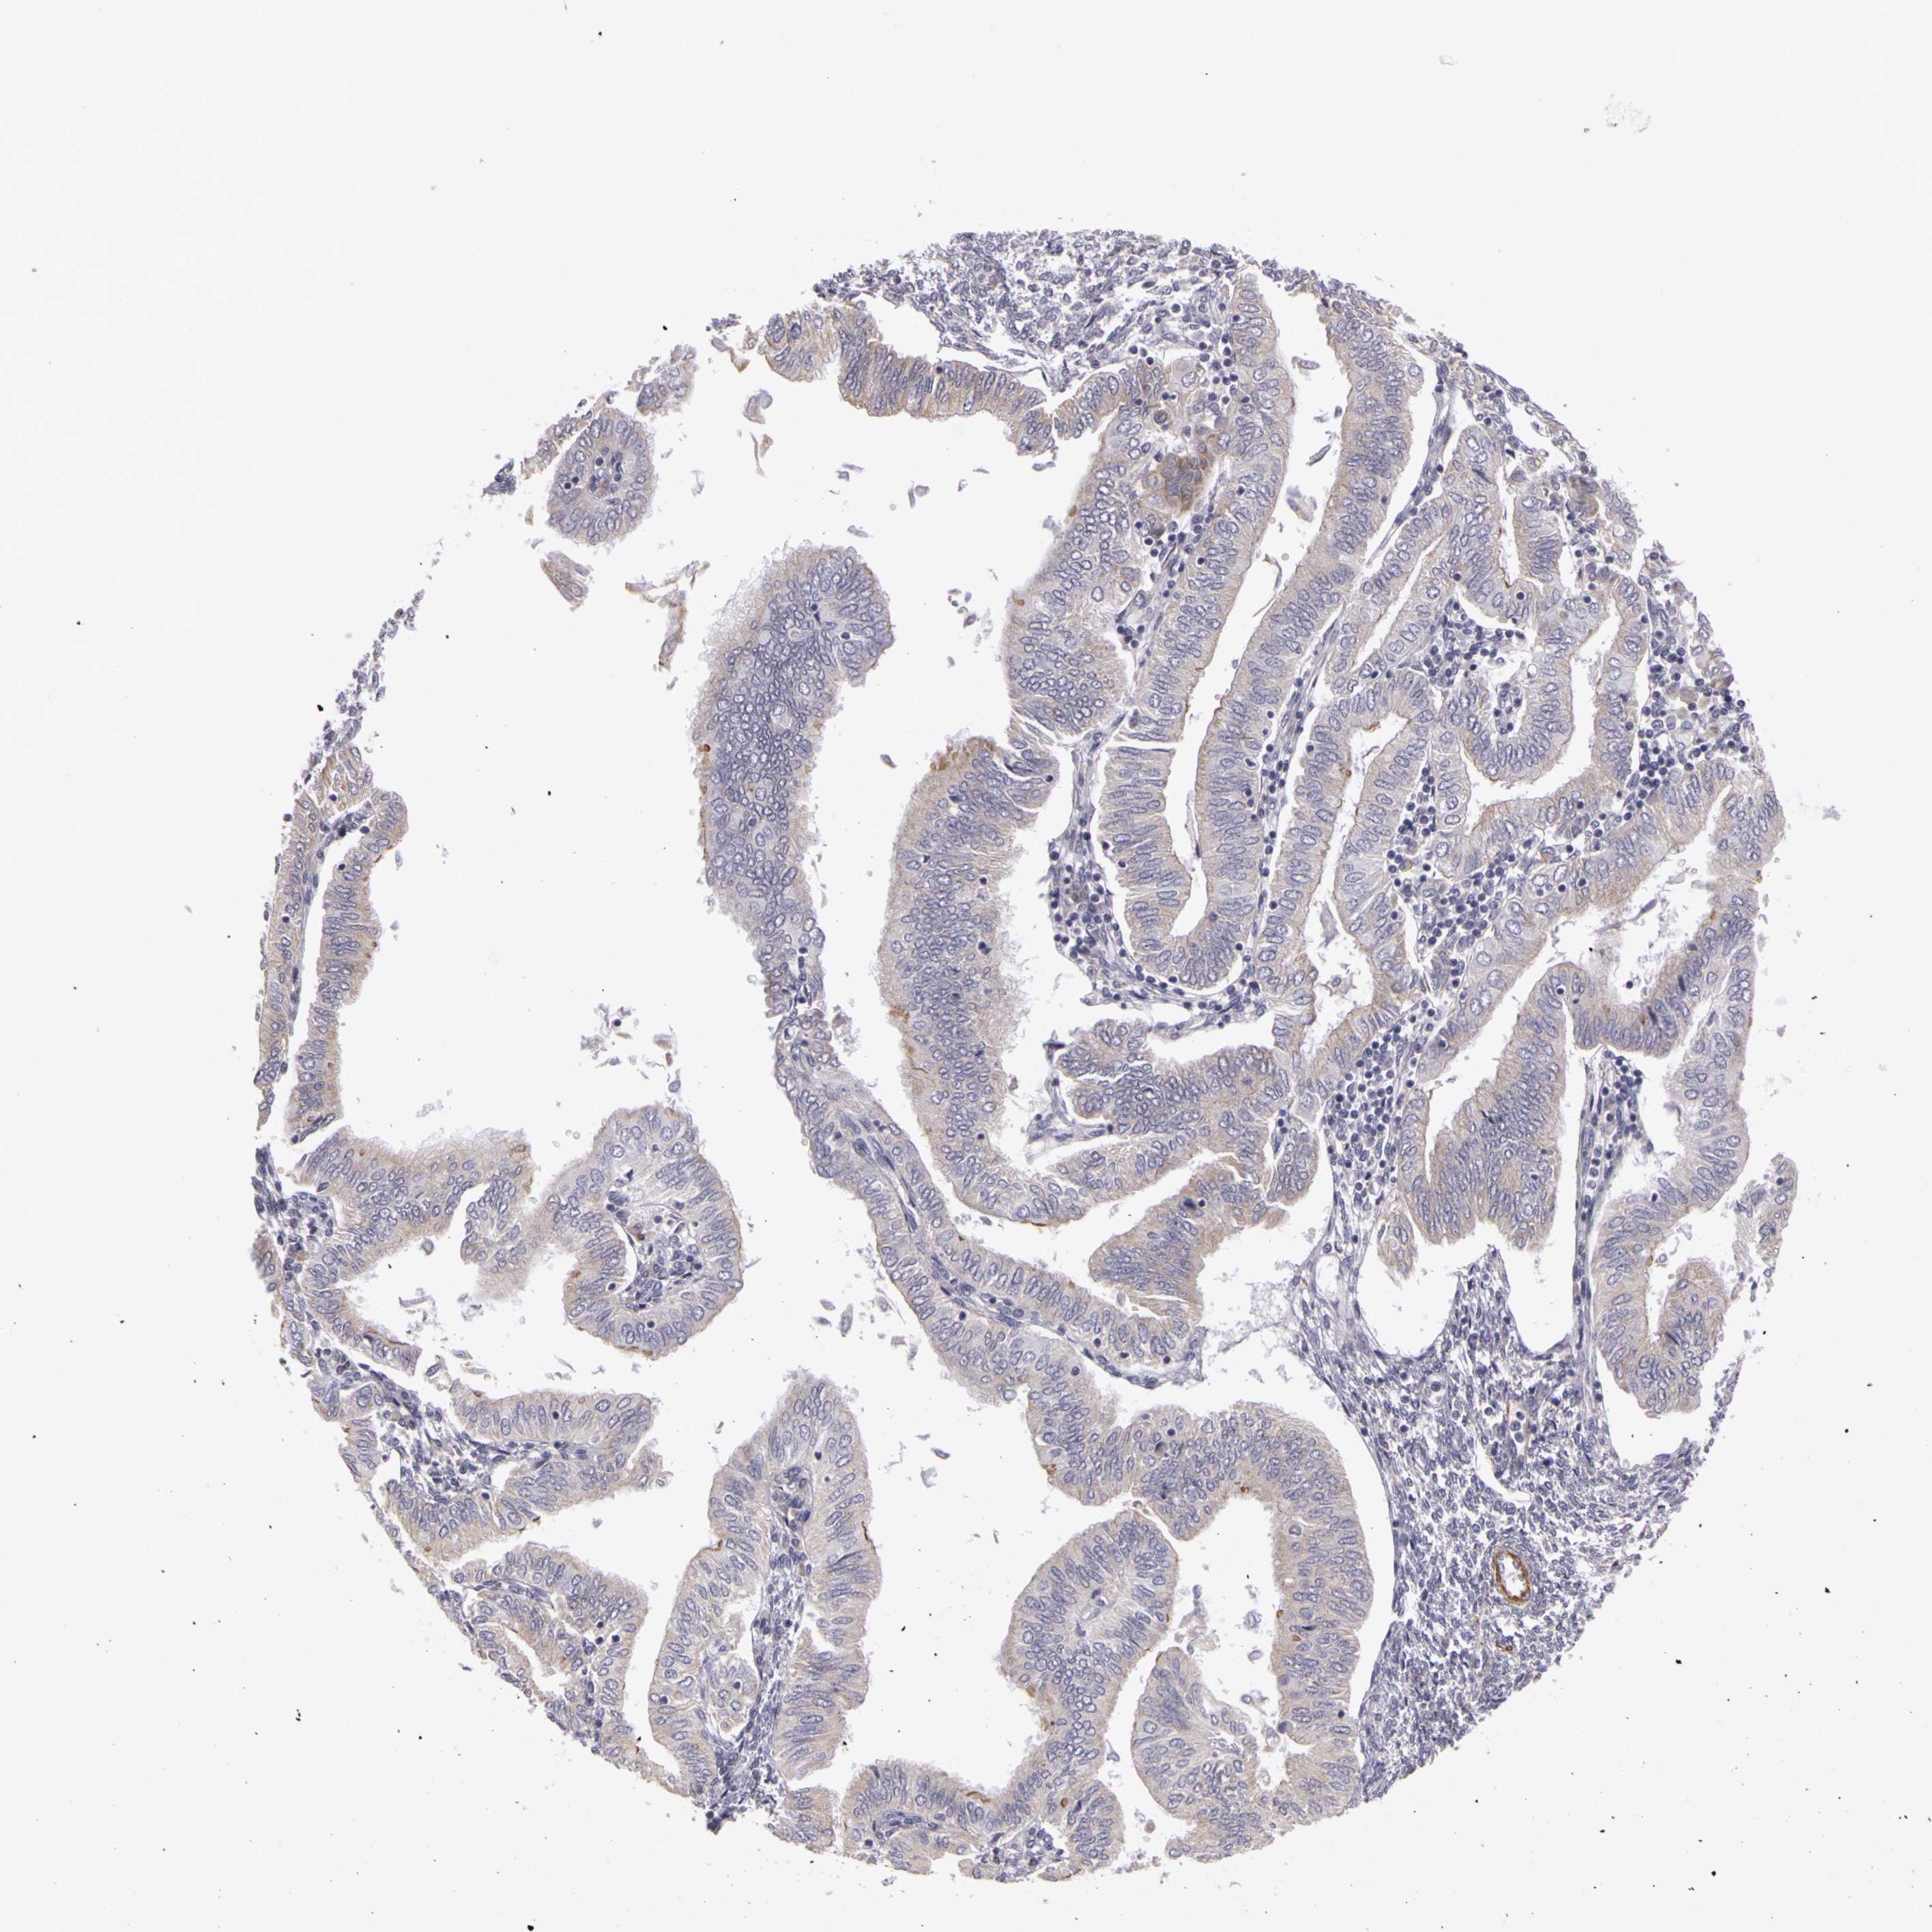

ENDOMETRIAL CANCER - Protein expressioni

A mouse-over function shows sample information and annotation data. Click on an image to view it in a full screen mode. Samples can be filtered based on level of antibody staining by selecting one or several of the following categories: high, medium, low and not detected. The assay and annotation is described here.

Note that samples used for immunohistochemistry by the Human Protein Atlas do not correspond to samples in the TCGA dataset.

Antibody stainingi

Antibody staining in the annotated cell types in the current human tissue is reported as not detected, low, medium, or high, based on conventional immunohistochemistry profiling in selected tissues. This score is based on the combination of the staining intensity and fraction of stained cells.

Each image is clickable and will lead to virtual microscopy that enables deeper exploration of all samples and also displays staining intensity scores, fraction scores and subcellular localization as well as patient and tissue information for each sample.

Antibody HPA001397

Antibody HPA012497

Staining

High

Medium

Low

Not detected

Intensity

Strong

Moderate

Weak

Negative

Quantity

>75%

75%-25%

<25%

None

Location

Nuclear

Cytoplasmic/membranous

Cytoplasmic/membranous,nuclear

Adenocarcinoma, NOS